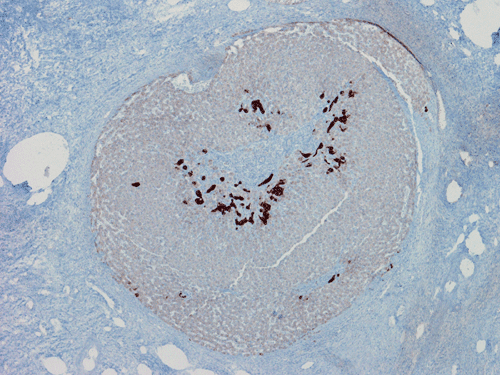

Histologically, the grossly notable nodules correspond to islands of cells separated by dense fibrous tissue  (Panel B). On medium magnification, the islands of cells have smooth, pushing margins (Panel C). The cells are quite similar to normal hepatocytes except that these islands do not have the general architecture of normal liver (Panel D). The liver plate varies from one to three cell thick is well demonstrated by reticulin stain (Panel I). In some areas there are some entrapped ductular structure consistent with bile ductules (Panel E and F) and they are well demonstrated by immunohistochemistry for cytokeratin 7 (Panel J and K). Most of these ductules are found around the fibrous scar or septa or at the edge of the nodules. Many abnormally large blood vessels are also noted and many of them are seen in the fibrous central scar (Panel G and H).

FNH is essentially a morphologic diagnosis. Immunohistochemically, they express hepatocellular markers such as Her Par 1. They are also positive for CAM5.2, polyclonal CEA, and alpha-1- antitrypsin. CD34 is positive in endothelial cells lining the cell plates. AFP and P53 are negative. CK7 is negative in the hepatocytes but they are useful in demonstrating the proliferating bile ductules. This use, is more of educational than diagnostic purposes.